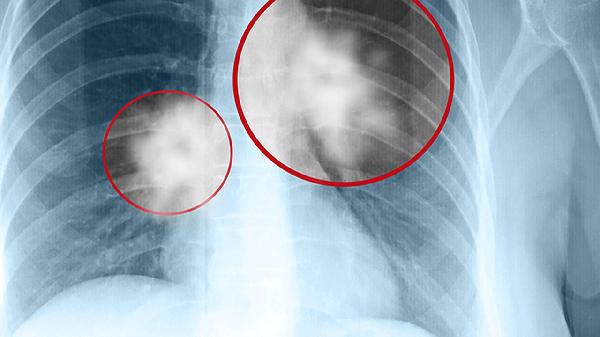

放射性肿瘤的潜伏期长短不一,这主要取决于多种因素的共同作用。通常情况下,接受大剂量辐射治疗的患者可能在数月到数年内出现放射性肿瘤的症状和体征。不过,这个时间并不是固定的,还会受到其他因素的影响。比如,年龄是一个重要因素,年轻人在接受放射治疗后,由于身体修复能力较强,潜伏期可能会较短。而老年人由于修复能力相对较弱,可能需要更长的时间才能显现出症状。

了解放射性肿瘤潜伏期的不确定性能够帮助医生更好地评估患者的病情,并制定相应的治疗方案。对于那些曾经接受过放射治疗的人,定期随访和检查是非常重要的措施。这不仅可以帮助及早发现任何潜在的问题,还能及时采取措施进行处理,避免病情的进一步发展。保持警惕和积极的态度,是应对放射性肿瘤潜伏期不确定性的有效方法。